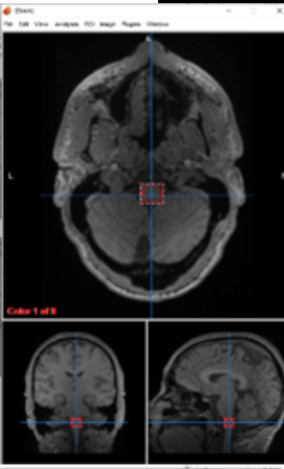

cerebellum

fine movements

cerebellum (vermis)

posture and balance

pons

involuntary functions, sleep, communication

Medulla

directs nerve signals